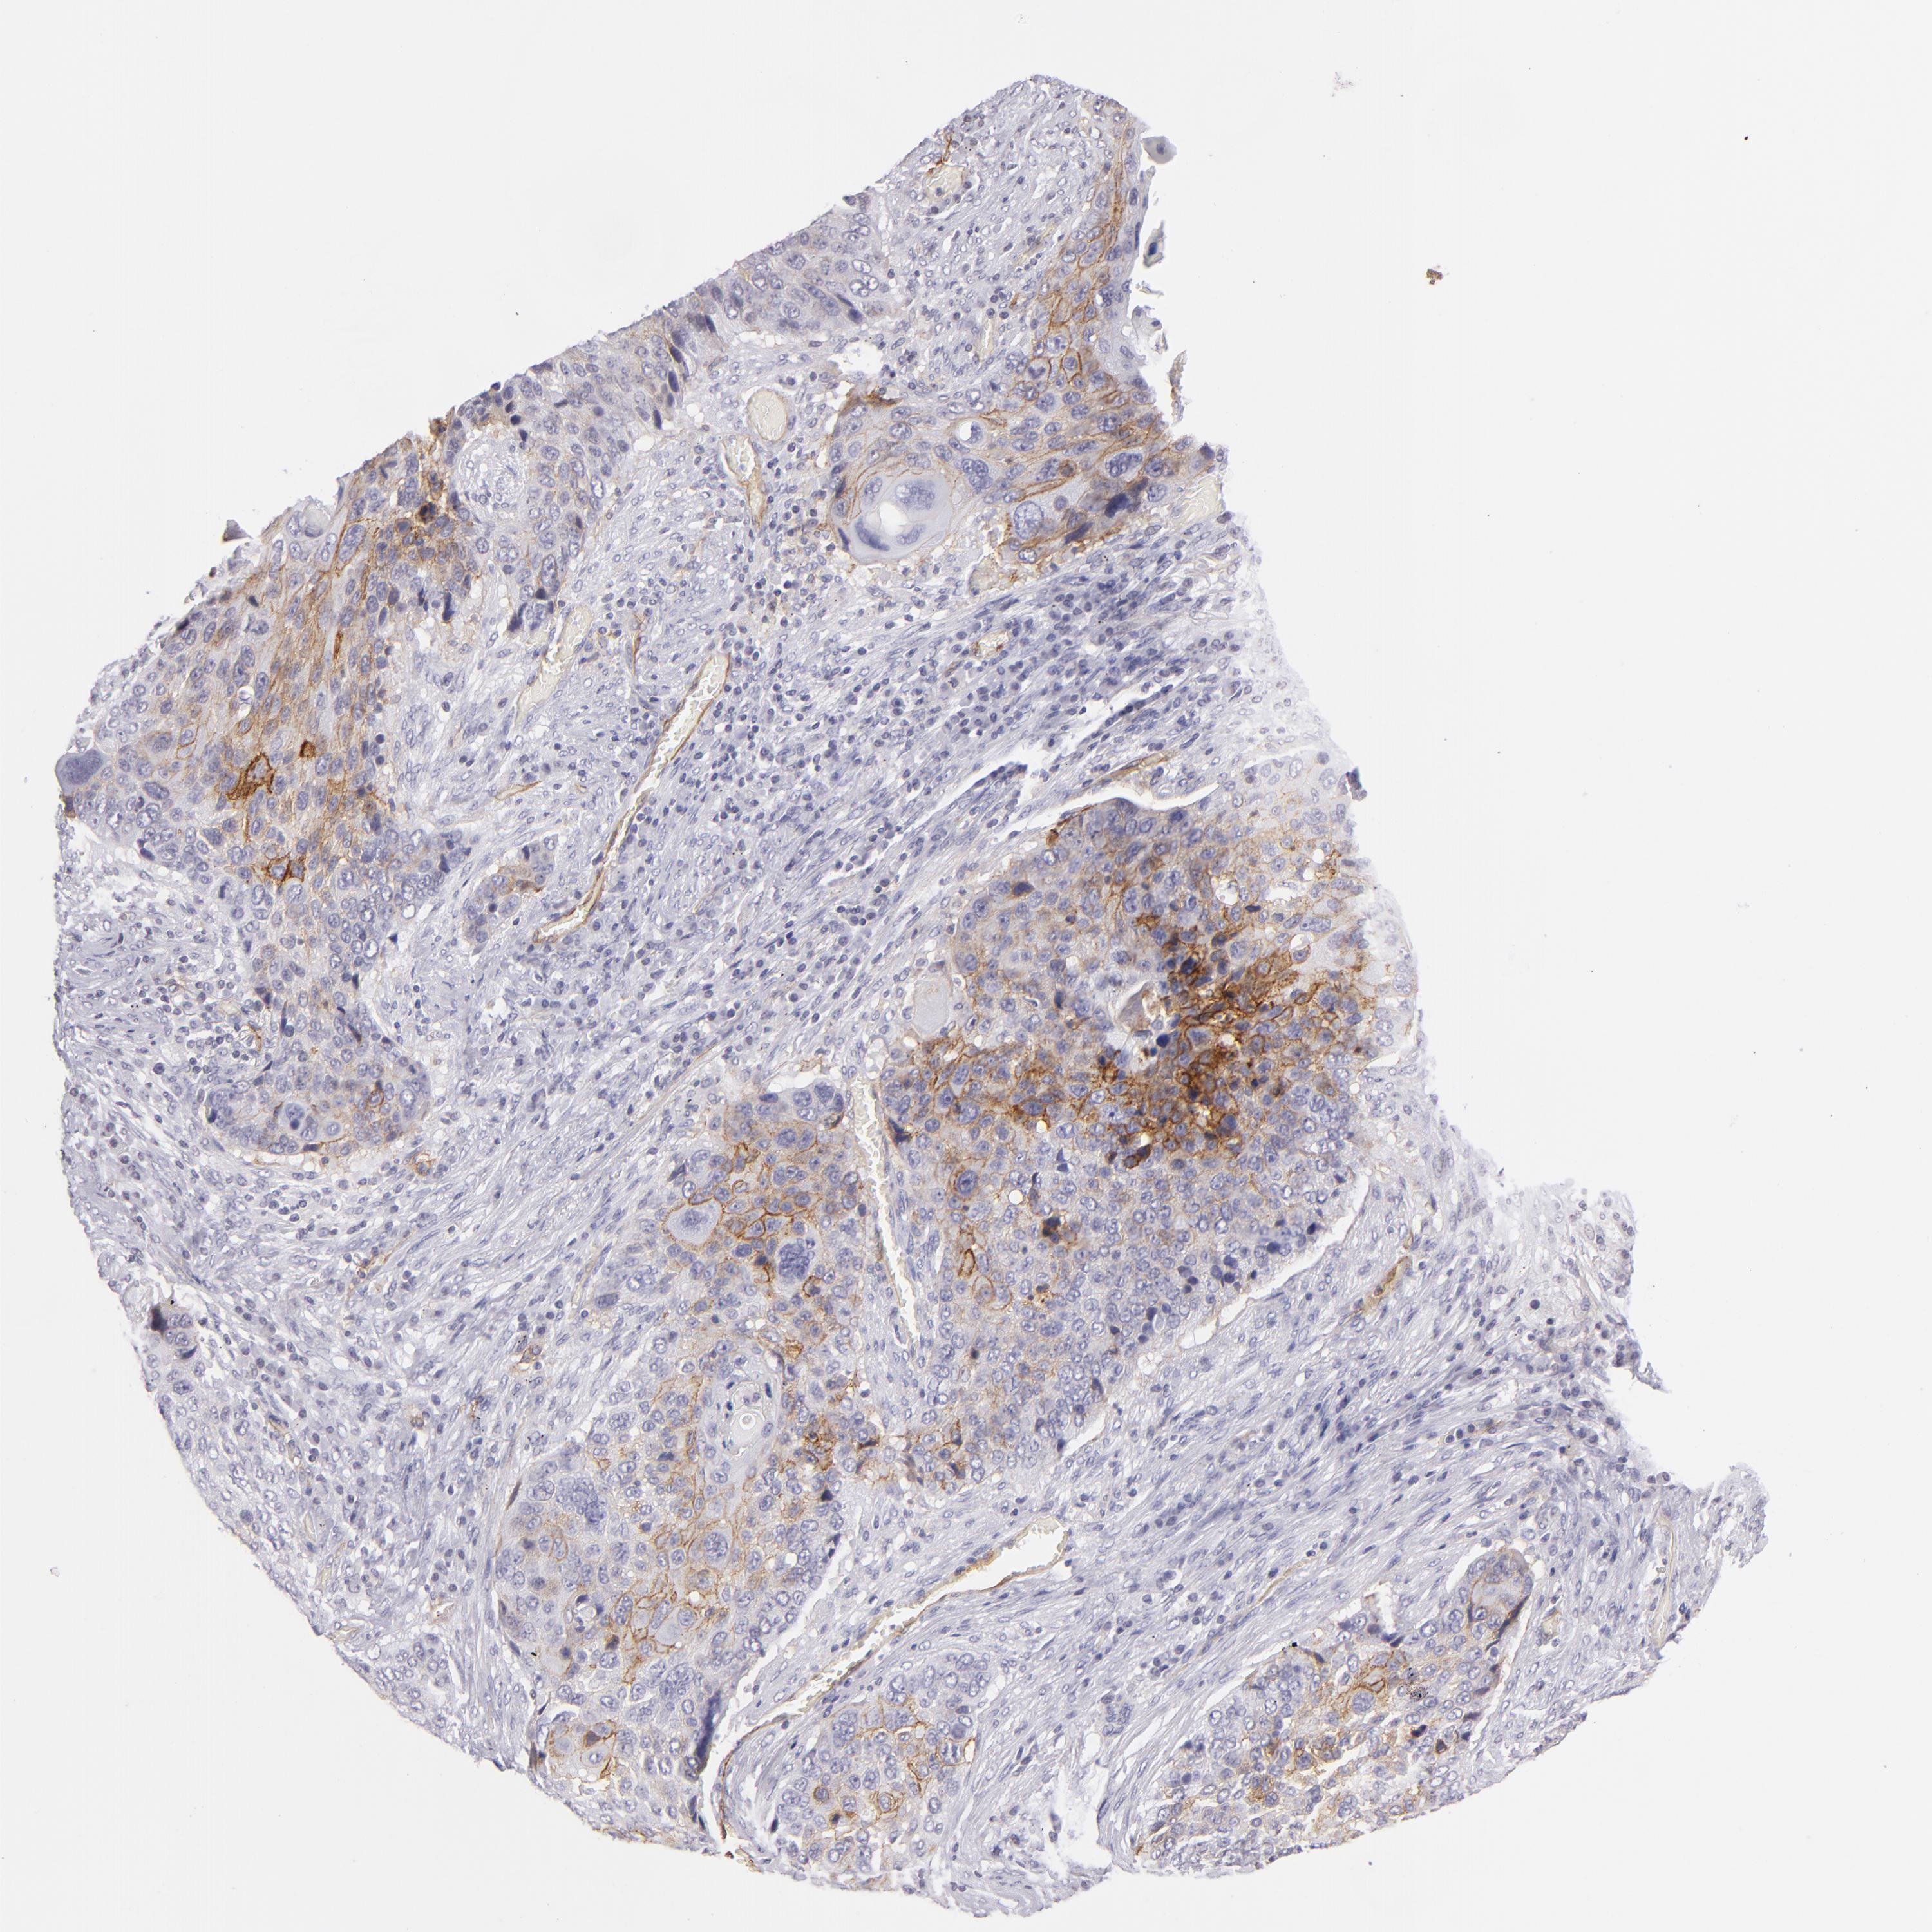

CANCER LUNG CANCER Show tissue menu

Lung cancer

Human cancer

Lung adenocarcinoma

Lung squamous cell carcinoma